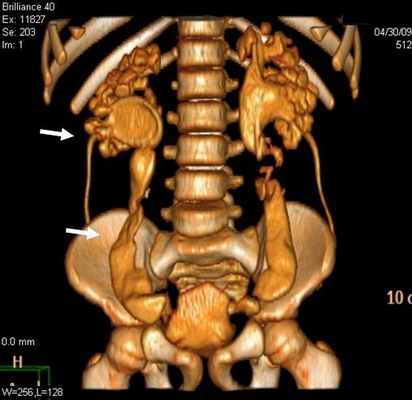

Дополнительные диагностические возможности открываются при реконструкции полученного изображения с применением тонких реконструируемых срезов (1,25 мм), а также построения мультипланарных реконструкций. При этом изменение со стороны мочеточника характеризовалось расширением (62,2%) и деформированием (29,7%) органа (рис 2.).

Рис 2. Уретерогидронефроз (a, б) у больных с пороками развития уретеровезикального сегмента

Стеноз устья мочеточника на МСКТ выявлен в 29 (78,4%) наблюдениях (рис 4). Данная патология у 17 детей была с обеих сторон, а 3 наблюдениях этот порок сочетался с уретероцеле и эктопией устьев мочеточника.

Рис 4. Стеноз устья мочеточника. Трехмерная реконструкция. Больной К., 6 лет. Деформирование мочеточников и сужение устья мочеточников